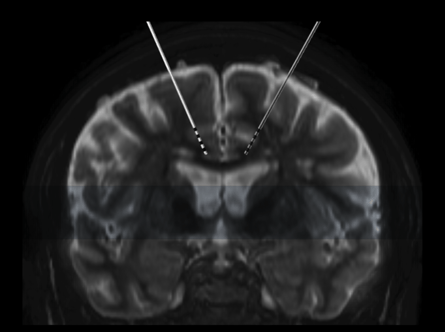

La référence Hunsche S, Sauner D, Runge MJ, Lenartz D, El Majdoub F, Treuer H, Sturm V, Maarouf M. Tractography-guided stimulation of somatosensory fibers for thalamic pain relief. Stereotact Funct Neurosurg. 2013;91(5):328-34 L'article Le faisceau spinothalamocortical (STC) est considéré comme étant la voie responsable dans la transmission des douleurs thalamiques. Le thalamus ou le bras postérieur de la capsule interne (BPCI) sont des cibles pour la stimulation cérébrale profonde...